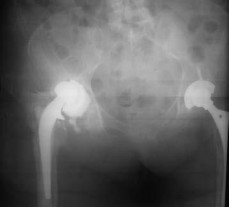

Figure 64 is the radiograph of a 77-year-old woman with a painful total hip arthroplasty (THA) who had surgery 15 years ago. Preoperative laboratory studies reveal a C-reactive protein (CRP) of 4 mg/L(reference range, 0.08-3.1 mg/L). Her serum white blood cell (WBC) count and differential values are within defined limits, and her erythrocyte sedimentation rate (ESR) is 35 mm/h (reference range, 0-20mm/h).

What is the next appropriate step in management of the patient?

Aspiration is appropriate in the setting of a failed total joint replacement when ESR and CRP are elevated,even with a normal systemic WBC count. A MRI scan of the hip is not useful in this setting. A labeled WBC scan is of no additional value when an aspiration of the hip is planned. Although multiple cultures should be obtained at the time of revision THA, preoperative aspiration is appropriate in this case. Most acetabular revisions can be accomplished with a cementless hemispherical component.

Supplemental fixation with screws is indicated. In this patient, the acetabular rim and columns are intact and the first choice is a cementless hemispherical component. Bilobed components have an unacceptably high failure rate and are not indicated when the acetabular rim is intact. A cemented all-polyethylene shell is not likely to achieve adequate long-term fixation with the sclerotic acetabular bone. An antiprotrusio device is indicated in the setting of severe bone loss or pelvic discontinuity. An antiprotrusio cage is the best choice in the setting of a pelvic discontinuity that has the capacity to heal. If the discontinuity does not have the capacity to heal, it can be treated in distraction with an acetabular allograft supported by a cage or custom triflange component. A large porous cup is not likely to achieve stable fixation and will require removal of more acetabular bone. A cemented acetabular component will not achieve adequate stability or fixation in the absence of additional support. Resection arthroplasty would not be the first choice in a potentially reconstructable situation. PREFERRED RESPONSE: 3